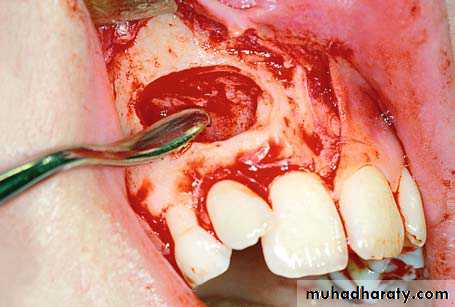

After careful reflection of the mucoperiosteum, part of the crown of the tooth may be exposed, or the entire crown may be covered by bone, resulting in protuberance at that site

reflection of the flap. Arrow points to the protuberance of bone, which indicates the position of the crown of the impacted tooth

Enough bone must be removed to expose the entire crown, so that the tooth may be extracted using forceps or an elevator. If the tip of the crown is positioned between the roots of the lateral and central incisors, there is a risk of injuring their roots during the exposure attempt. That is why extraction of the canine must be achieved using the technique of separating the crown from the root.

Removal of bone using a round bur, to expose the crown of an impacted tooth